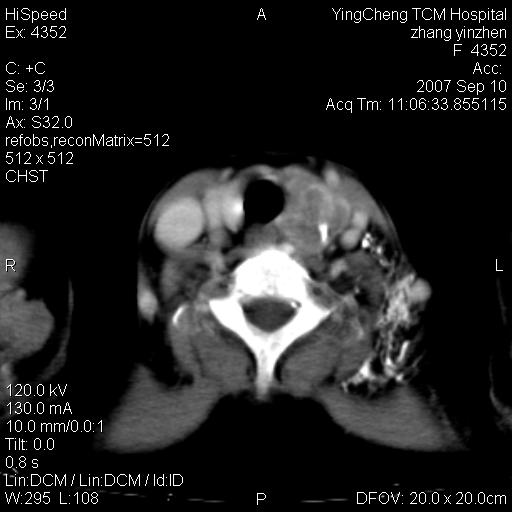

以下是引用卜一在2007-9-18 14:41:00的发言:[br]右肺肿块:毛刺+胸膜凹陷征+供血血管+浅分叶+强化。支持:周围性肺癌 !另:左侧甲状腺腺瘤!

以下是引用夏季在2007-9-18 11:00:00的发言:[br]1。右肺肿块,周围有短毛刺,肺门侧有血管与其相连,胸壁侧有胸膜凹陷征,考虑周围性肺癌 2。左侧甲状腺软组织肿块,内有高密度钙化灶,考虑左侧甲状腺腺瘤。